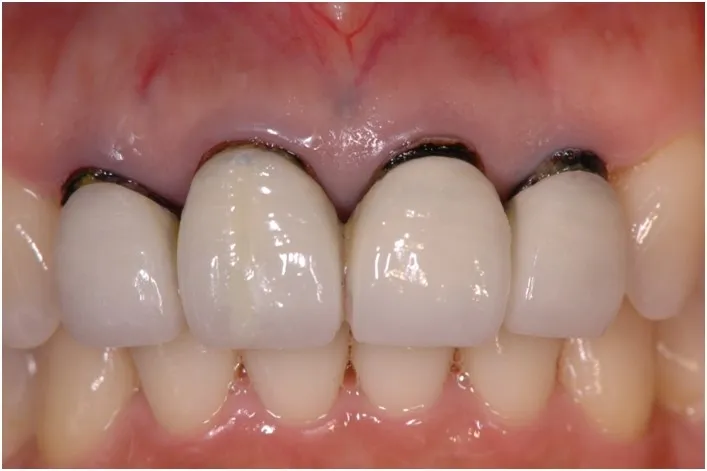

【治療前】

【治療後】